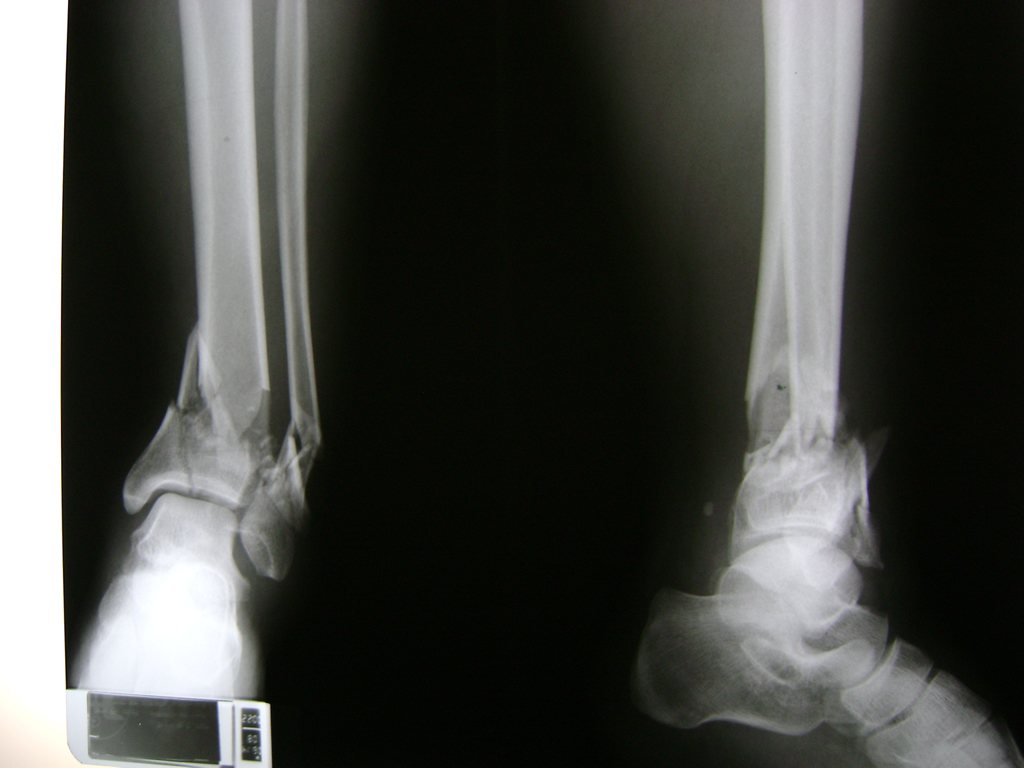

Una fractura de tobillo es la rotura de uno o más de los huesos del tobillo. Estas fracturas pueden ser:

- Parciales (el hueso está sólo parcialmente fisurado, no del todo).

- Completas (el hueso está perforado y está en 2 partes).

- Producirse en uno o ambos lados del tobillo.

Algunas fracturas de tobillo pueden requerir cirugía si:

- Los extremos de los huesos están desalineados entre sí (desplazados).

- La fractura se extiende hasta la articulación del tobillo (fractura intra-articular).

Cuando se necesita cirugía, es probable que esta implique el uso de clavijas de metal, tornillos o placas para sostener los huesos en su lugar mientras la fractura se consolida. Los elementos de soporte pueden ser temporales o permanentes.